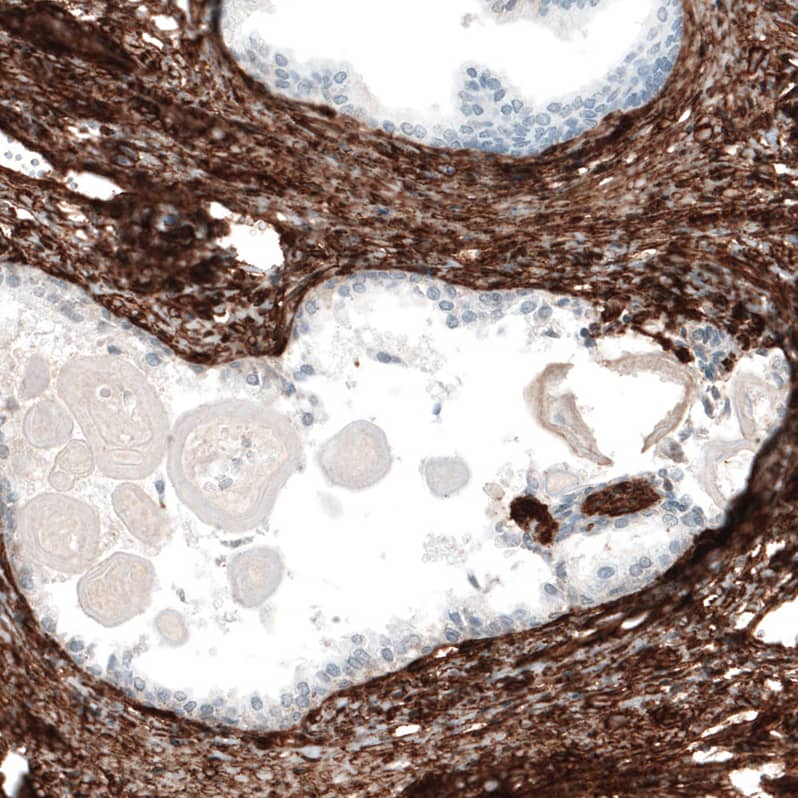

Staining of human placenta shows strong membranous positivity in blood vessels and loose connective tissue of chorionic villi.